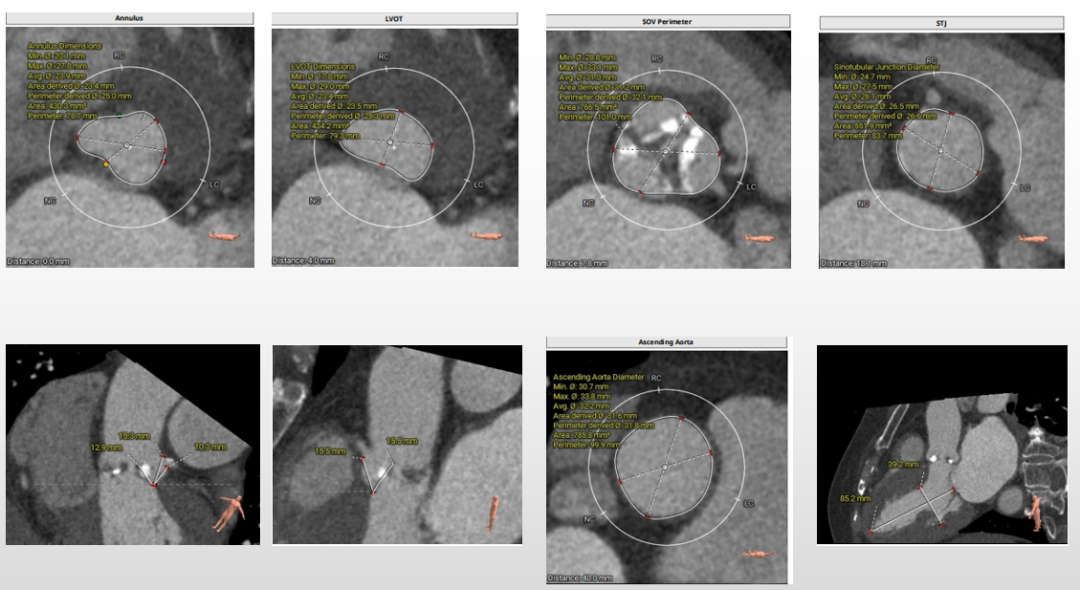

第一例术前评估

主动脉根部评估

三叶式主动脉瓣,瓣叶增厚,流出道呈敞口状,左右冠均有钙化,由于瓦氏窦、STJ内径小,左冠窦瓣叶长度>瓣叶附着缘到冠脉开口的距离,VTC3.1mm,术中冠脉阻挡风险较高。

瓣环上解剖结构评估

中度钙化,瓣上6-8mm限制最重,根据瓣环及瓣上情况,选18mm球囊预扩、AV23瓣膜。

外周血管及主动脉弓解剖

双侧髂总动脉轻度扭曲少量钙化,腹主动脉折角明显,入路血管直径尚可,选择右侧为主入路,左侧为辅入路。

第二例术前评估

三叶式主动脉瓣,瓣叶增厚,流出道呈直筒状,由于瓦氏窦、STJ内径小,左冠窦瓣叶长度>瓣叶附着缘到冠脉开口的距离,术中有冠脉阻挡风险。

重度钙化,瓣上4-8mm限制最重,根据瓣环及瓣上情况,选20mm球囊预扩、AV23瓣膜。

双侧髂总动脉轻度扭曲少量钙化,双侧髂外动脉内径细,左侧内径稍好,最细5.2mm,选择左侧为主入路,右侧为辅入路。

第三例术前评估

三叶式主动脉瓣,瓣叶增厚,流出道呈敞口状,升主轻微扩张,左心室偏大,左冠窦瓣叶长度>瓣叶附着缘到冠脉开口的距离,术中有冠脉阻挡风险。

无钙化,根据瓣环及瓣上情况,选AV29瓣膜。

双侧髂主动脉轻度扭曲无钙化,双侧入路内径良好,选择右侧为主入路,左侧为辅入路。